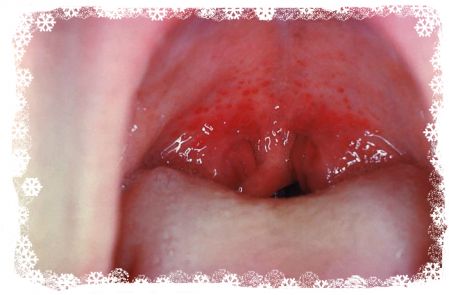

Прыщики не похожи на эти?

attached-photo

у нас такое было. это вирусная ангина?

да, герпетическая. плюс на ладонях и подошвах высыпает, на попе может быть.